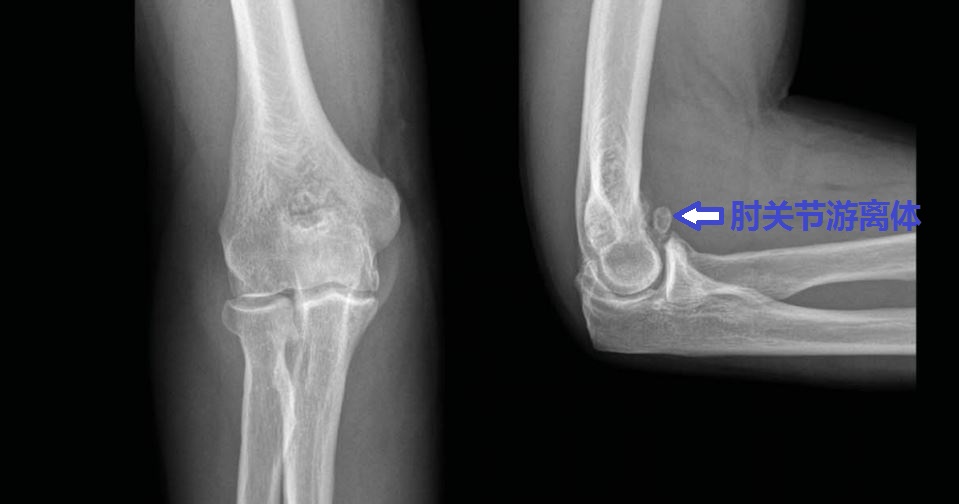

我们徐州1000万人口。其中有很多和您一样肘关节伸屈不行的患者。去年习*平近**主席两次到徐州视察进一步推进了我们徐州的快速发展。我们徐州发展过程中需要很多建筑工人。建筑工人师傅中有很多人来找我看肘关节问题。很多人都是由于肘关节骨性关节炎、肘关节游离体、肘关节骨质增生导致的肘关节僵硬。

伸不直往往是因为:1、尺骨鹰嘴骨质增生;2、肱骨远端后侧的尺骨鹰嘴窝骨质增生填塞;3、肘关节前侧的关节囊挛缩;4、肘关节内的游离体卡住了;等等。

屈不下来往往是因为:1、尺骨冠状突骨质增生;3、肱骨远端前面的尺骨冠状突窝骨质增生;4、肘关节后侧的关节囊挛缩;等等。